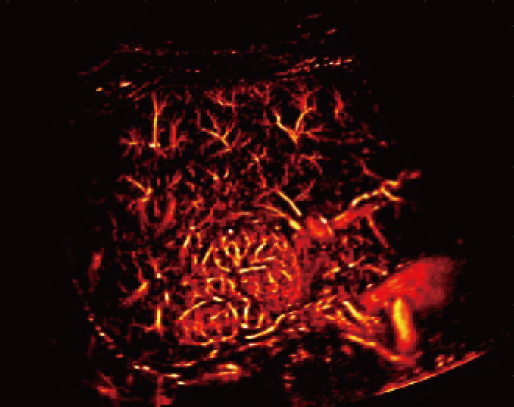

Aangestuurd door het AIT platform levert de Resona A20 een alles-in-├®├®n, ge?ntegreerde oplossing voor beeldvorming met superresolutie, iets wat voorheen moeilijk haalbaar was. SR CEUS onthult de ingewikkelde microcirculatiedetails van laesies op micronniveau, wat helpt bij onderzoeken naar microcirculatoire perfusie in oncologie.

Mogelijkheden voor microvasculaire detectie

Focale nodulaire hyperplasie | Dichtheidskaart